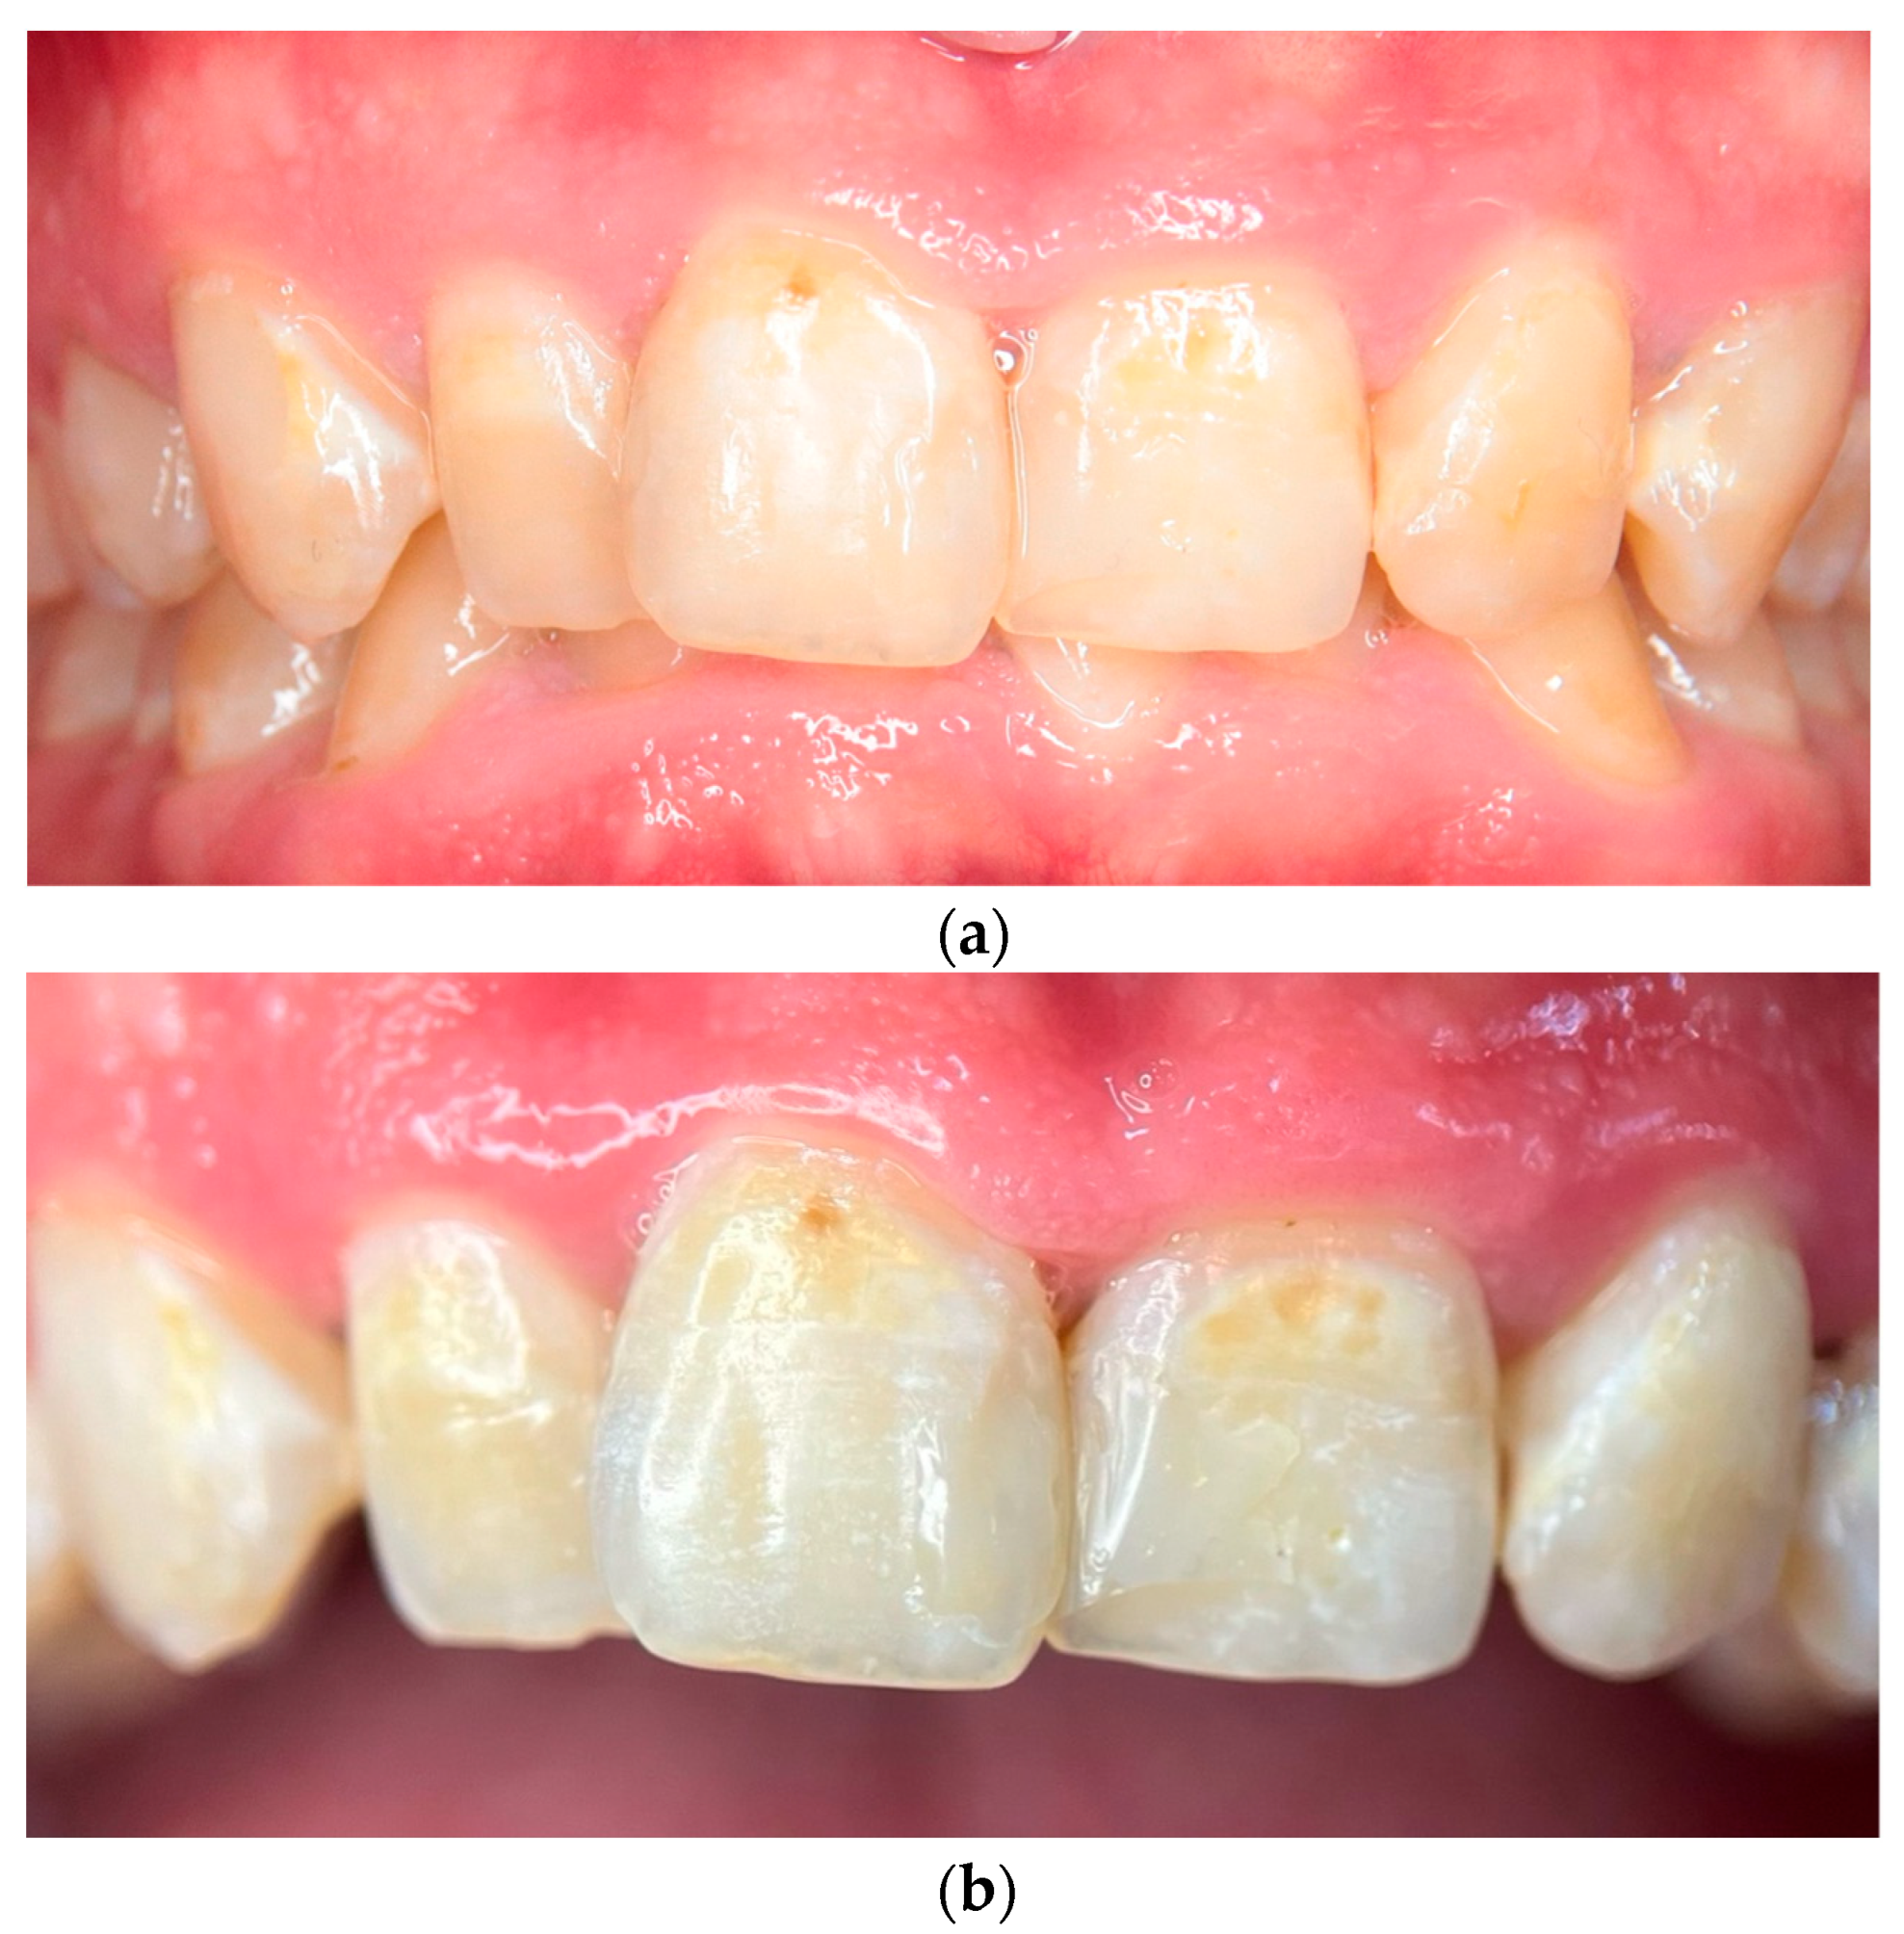

At the 120-day follow-up visit, a full examination showed significant remineralization, particularly on the upper anterior teeth, along with the complete resolution of gingivitis, as there were no signs of inflammation or bleeding upon probing (Figure 2a). A close-up view of the central incisors at this stage emphasized the improved enamel surface and the overall progress in remineralization. This follow-up macro photograph was captured using the same 100 mm macro lens and standardized conditions, ensuring comparability with the baseline images (Figure 2b).

Figure 2.

(a) Intraoral photograph at the 120-day follow-up showing improvement in enamel remineralization and reduction of discoloration. (b) High-resolution close-up of the central incisors at 120-day follow-up, emphasizing the improved enamel surface and successful remineralization. The image was captured under dry conditions to enhance visibility of remineralization patterns.